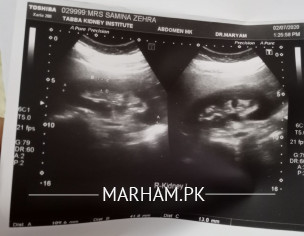

my mother is having intense kidney pain, in first few days doctor only advised nuberol forte saying it muscle pain. Later she was advised Ciprofloxacin 500mg twice, Denzene ds thrice a day and Piroxicam twice aday.. but no relief in pain.. please help Renal kidney tests and ultrasound attached.

As she is Diabetic, so it is important to do her urine DR, and CS first before advising any antibiotics. For pain Ill advise tab. Anafortan plus 2 tabs three times a day

In addition to what Dr Irfana Hassan have

advised,please get CT KUB to see why both kidneys PC system are dilated and then get a urologist review . Also do RFTs .